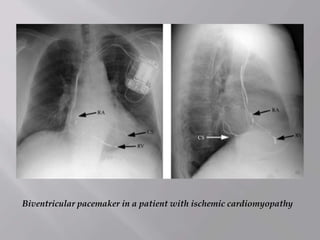

Biventricular pacemaker in a patient with ischemic cardiomyopathy

Biventricular pacemaker ina patient with ischemic cardiomyopathy